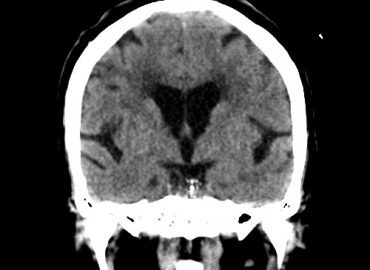

Femenino, 71 años. Sospecha de ACV agudo.

MASCULINO 19 AÑOS APP: NIEGA. ATX: NIEGA. AHF: NIEGA MH: NIEGA MC: CEFALEA, CONVULSIONES

Paciente de sexo masculino de 10 años de edad, consulta por cefalea

Paciente masculino de 10 años de edad que consulta por convulsiones.